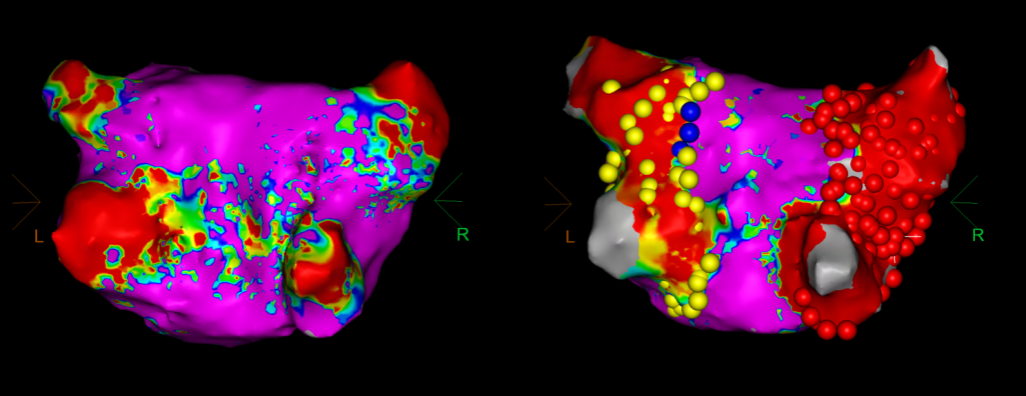

手术在介入导管室的通力配合下进行,姜馨主任、薛建颖主治医师、刘成峰医师密切配合,术中通过右侧股静脉送入心腔内超声(ICE)至右心房,排除左房血栓后成功指导精准房间隔穿刺,沿可调弯鞘管送入锦江心脏脉冲电场消融导管至左房,构建左房三维解剖模型并行基质标测,标测显示左房基质尚可,分别行左侧、右侧肺静脉消融。消融参数:1800v、400ms、400μs,共放电消融148次(消融左上肺静脉时转复为窦性心律),验证双肺静脉均隔离。术后重新标测显示所有肺静脉均已急性阻滞,消融效果理想,肺静脉前庭损伤范围也达到了预期的标准,同时ICE监测未见明显心包积液。手术仅用时30分钟,时间明显缩短,手术过程精准高效。术后患者恢复情况良好并顺利出院。术后1月复查心电图提示窦性心律,心脏超声提示心脏较前明显缩小,收缩功能明显改善,射血分数由25%提升至40%,心功能标记物NT-proBNP 恢复正常,仅54pg/ml。

图5 消融前后基质标测提示肺静脉消融效果明显